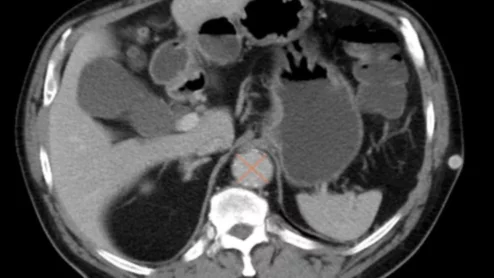

imaging radiology money scans compensation pay dollar

The payment program spent $484 million on 15 different low-value imaging services, a figure that balloons to $584 million when factoring for out-of-pocket costs.